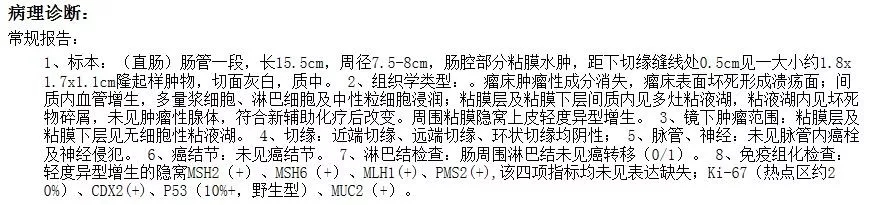

幸运的小雅按治疗计划如期接受了腹腔镜低位直肠癌适形保肛术+NOSE手术,术后小雅遵照赵医生的指导进行术后肛门功能康复训练,半年后腹部穿刺切口已经很难辨认。

华哥和华嫂是幸运和幸福的,华哥如期接受了腹腔镜低位直肠癌适行保肛术+临时性回肠造口术。术后积极进行术后肛门功能康复训练,目前术后一个月,华哥肛门功能恢复满意,排尿正常、性功能正常—华哥雄风依旧。

腹腔镜术后一周腹部照片